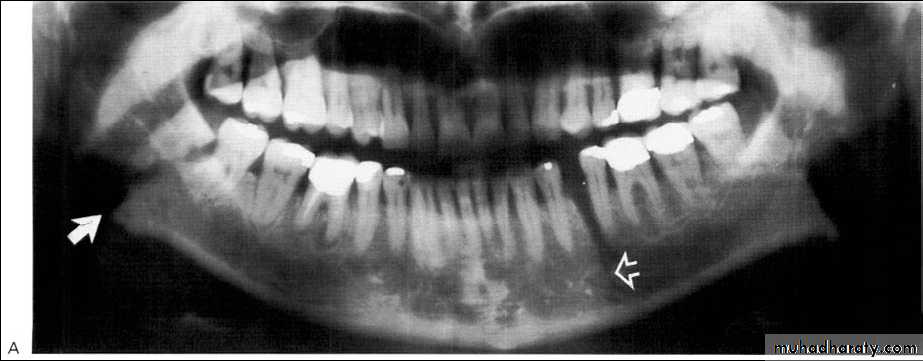

Odontogenic keratocyst:*This cyst develops from the epithelium of the dental lamina instead of the normal tooth which is therefore typically missing from the series.

*The regional teeth are vital.

*Shape: Oval, extending along the body of the mandible with little

mediolateral expansion.

*Minimal displacement of the adjacent teeth , rarely resorbed

Extensive expansion within the cancellous bone.

*Treatment by surgical excision.

A 11-year-old female with swelling on the right side.

impacted canine